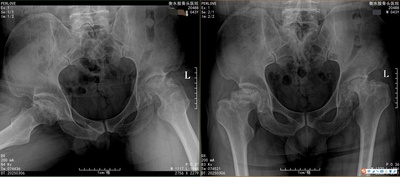

在医疗领域,股骨头坏死一直被视为难题,“不死癌症”的定论曾让无数患者陷入绝望。然而,衡水股骨头医院以其独特的治疗理念和方法,为众多患者带来了新的希望。衡水仁安中医骨科医院,专注于保守治疗股骨头坏死。多年来,在李红印院长与张春荣院长的引领下,医院坚守核心发展目标,在“科学治疗”“康复锻炼”“预防保健”三大方向上取得了显著成果。李红印院长是医院的灵魂人物之一。他来自河北省衡水市枣强县,毕业于河北...

衡水仁安中医骨科医院衡水股骨头医院是一家专注于股骨头坏死保守治疗的专科医院。地址位于河北省衡水市桃城区人民东路2222,前身为“衡水股骨头坏死研究所”,现为一家集医疗、科研、教学于一体的二级中医骨病专科医院以中西医结合治疗股骨头坏死为核心特色,研发的“李氏三联疗法”,在保守治疗股骨头坏死领域获得了多项国家专利和科研成果。患者群体覆盖全国多个省市及海外华人地区,部分国际患者也慕名前来就诊。